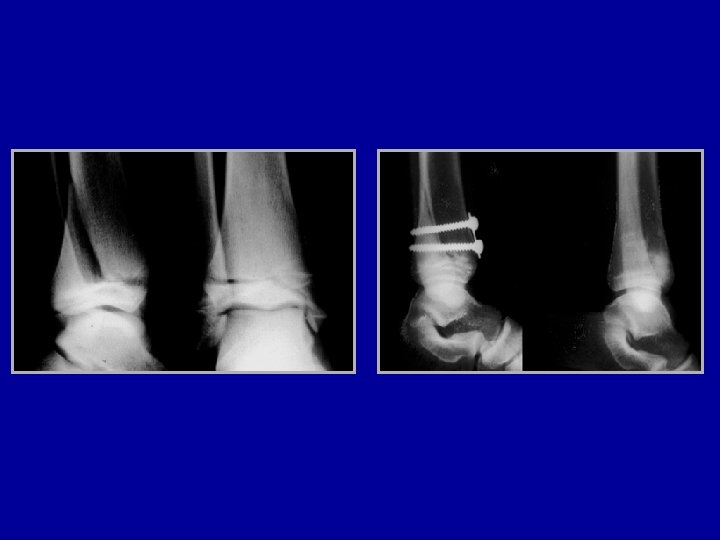

Malléole interne de type 3 avec malléole externe de type 1

Traitement par une vis interne épihysiodèse Photo F. Chotel

Salter III Vissage Photo F. Chotel